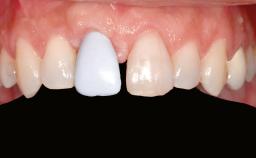

Shell Technique for Horizontal and Vertical Maxillary Bone Augmentation in a Partially Edentulous Patient with Aggressive Periodontal Disease

A 46-year-old woman was referred for treatment whose main complaints were mobility of her fixed partial dentures (right maxilla and left mandible) and periodontal bleeding during function. She also reported having taken systemic antibiotics to treat recurrent swelling in the area of the upper left molars. The patient had not seen a dentist for at least 2 years. She did not smoke and had no history of major systemic disease other than two minor orthopedic procedures some years back. The first-visit examination revealed poor plaque control, tooth mobility, periodontal disease, and a residual dentition widely associated with deep periodontal pockets.